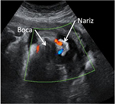

Ecografía Embarazo 2D y 3D - TERCER TRIMESTRE